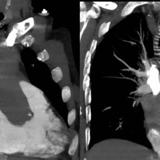

LV enlargement

RV enlargement